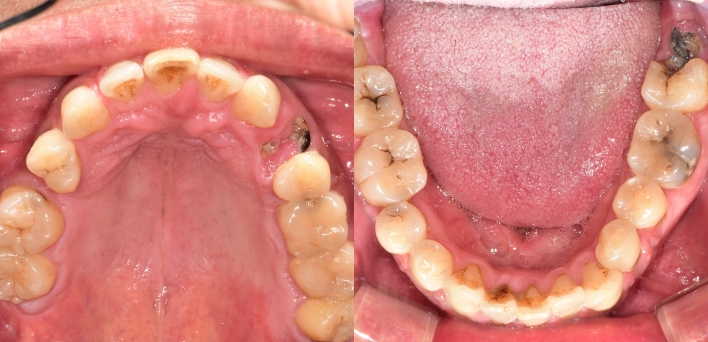

임플란트 : 손 ** 님 (50대)

After After

2020.02.30

위, 아래 6개씩 식립

디지털 풀아치 임플란트

임시 치아라고 조심하라고 하셨는데 수술하고 맛동산까지 먹었습니다.

임플란트 Before & After

The seoul dental clinic